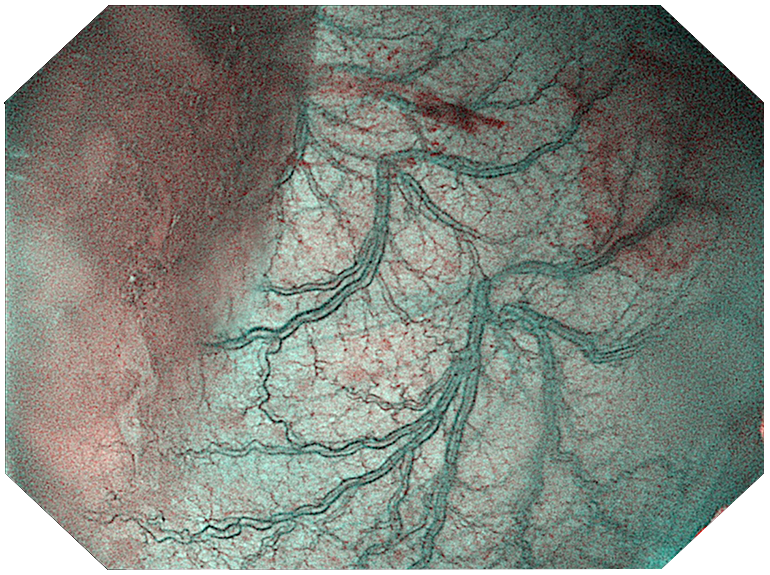

Три режима оптической хромоэндоскопии

Оснащен 4 светодиодными источниками света высокой яркости с независимым управлением, обеспечивающими многоспектральный режим окрашивания «белый свет + 3 спектра CBI». Спектральное окрашивание может повысить визуальный контраст между нормальной тканью и повреждениями, тем самым улучшая выявляемость небольших повреждений. Технология оптического окрашивания (CBI) – удобный и эффективный инструмент для выявления раннего рака, опухолевых и воспалительных процессов.

CBI regular позволяет легко выявлять поражения слизистой оболочки и подчеркивать распределение подслизистых сосудов. |  |

Три режима оптической хромоэндоскопии (CBI). Многоспектральная визуализация с 4 светодиодами высокой яркости:

- CBI regular — визуализация слизистой и подслизистых сосудов.